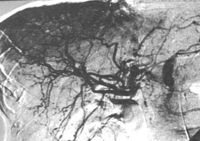

Angiografia renal mostrando aneurismas e microaneurismas

Do acervo do Dr Loic Guillevin